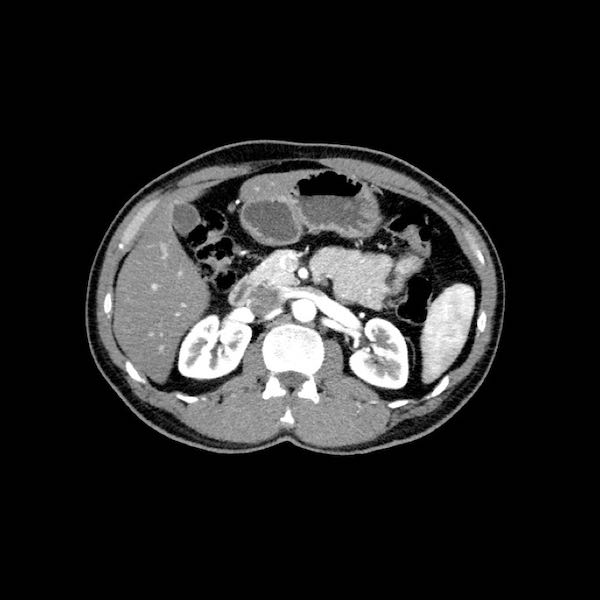

Việc sử dụng tái tạo đa mặt phẳng (multiplanar reformation) giúp cải thiện hiệu quả chẩn đoán tổng thể của CT, như được minh họa trong trường hợp này.

Tái tạo mặt phẳng coronal cho thấy một khối u nhỏ ở đầu tụy (đầu mũi tên) gây tắc nghẽn ống mật chủ.

Có vẻ chỉ có tiếp xúc hạn chế với tĩnh mạch cửa (mũi tên).

Tiếp tục xem các hình ảnh tiếp theo.